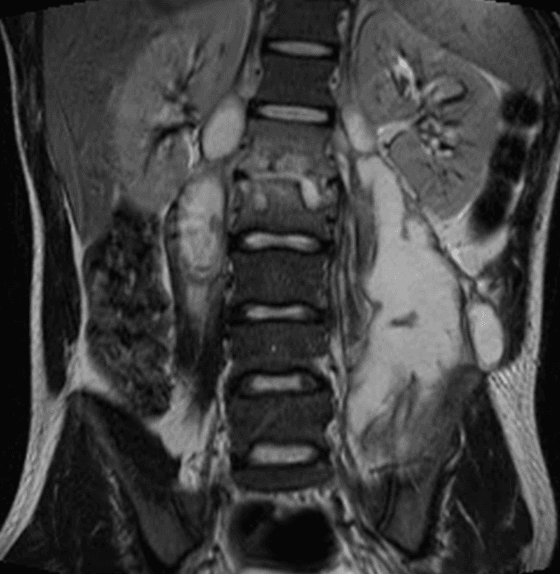

Paciente do sexo masculino, 28 anos, com dor lombar crônica agudizada após trauma direto.

Figura 2.